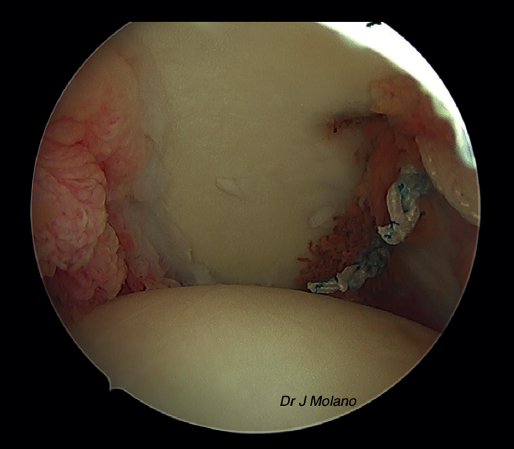

Posteriormente, se realiza el remplissage por vía artroscópica. Se coloca el artroscopio en el portal anterosuperior y se emplean el anterior y el posterior como portales de trabajo. Desde el portal posterior se realiza el curetaje/raspado superficial de la lesión de Hill-Sachs para conseguir una superficie sangrante. Tras ello, se colocan 2 implantes de tipo Iconix® (Stryker, Kalamazoo, MI, USA) (cargados con 2 hilos de sutura cada uno) desde el portal posterior próximos a la parte más medial del defecto de Hill-Sachs. Se recupera cada cabo de sutura de manera independiente a través del tejido capsular/infraespinoso con una pinza grasper, quedando estos en la misma línea mediolateral para ser anudadas sobre el infraespinoso al final del tiempo artroscópico(14) (Figuras 2 y 3).

Figura 3. Visión artroscópica desde el portal superior de un hombro derecho. Se observa Hill-Sachs tras pasar las suturas de remplissage, antes del anudado final.